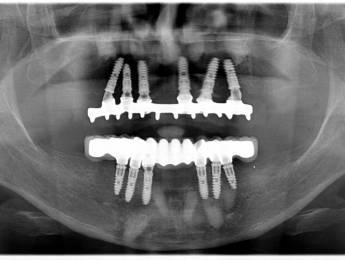

Ennek a kedves hölgynek 20 éves álmát váltottuk valóra. 20 évig hordott kivehető fogsorokat. 12 implantátum beültetése után alsó és felső fixen rögzített hidakat készítettünk. Nincs többé kivehető - evéskor, beszéd közben - elmozduló fogsor. Javult a rágási hatékonyság is, amely az egészséges táplálkozás szempontjából is nagyon fontos tényező.